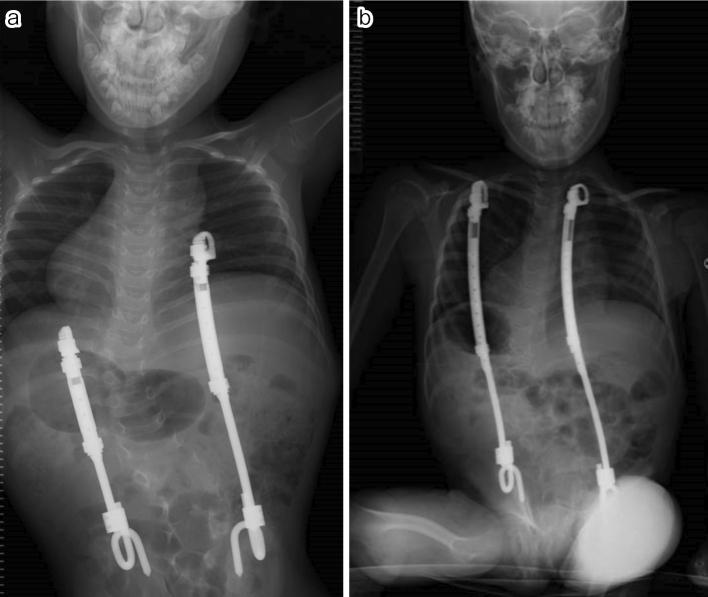

Case 1. A 10-year-old male underwent T8-S posterior fixation followed by multiple augmentations using allografts at the lumbosacral junction for delayed union. All additional procedures with bone graft using a posterior approach failed to achieve bone union; however, additional rigid fixation at the pubic symphysis resulted in a successful lumbosacral bone union. Case 2. A 6-year-old male underwent vertical expandable prosthetic titanium rib (VEPTR) surgery with multiple rod extension procedures. Subsequently, at the age of 10 years, a combined two-stage anterior (L1-3) and posterior (T8-iliac) fixation with T9 hemivertebrectomy was performed. As a result of subsequent nonunion with screw loosening, additional rigid fixation at the pubic symphysis was performed 1 month after posterior fixation. Bone union was finally achieved 1 year after all the surgical interventions.

病例1。一名10岁男性接受了T8 - S后路固定术,随后在腰骶部交界处使用同种异体骨进行了多次增强手术以促进延迟愈合。所有采用后路植骨的额外手术均未能实现骨愈合;然而,耻骨联合处的额外坚强固定导致腰骶部成功骨愈合。病例2。一名6岁男性接受了垂直可扩张人工钛肋骨(VEPTR)手术及多次棒延伸手术。随后,在10岁时进行了两阶段联合前路(L1 - 3)和后路(T8 - 髂骨)固定并进行了T9半椎体切除术。由于随后出现螺钉松动导致不愈合,后路固定术后1个月在耻骨联合处进行了额外的坚强固定。在所有手术干预1年后最终实现了骨愈合。